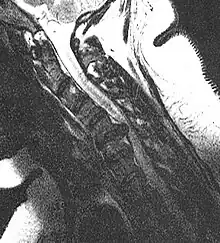

MRI scan of cervical disc herniation between C5 and C6 vertebrae. -

MRI scan of cervical disc herniation between C6 and C7 vertebrae -

Cervical disc herniations occur in the neck, most often between the fifth and sixth (C5–6) and the sixth and seventh (C6–7) cervical vertebral bodies. There is an increased susceptibility amongst older (60+) patients to herniations higher in the neck, especially at C3–4.[22] Symptoms of cervical herniations may be felt in the back of the skull, the neck, shoulder girdle, scapula, arm, and hand.[23] The nerves of the cervical plexus and brachial plexus can be affected.[24]

- Magnetic resonance imaging is the gold standard study for confirming a suspected LDH. With a diagnostic accuracy of 97%, it is the most sensitive study to visualize a herniated disc due to its significant ability in soft tissue visualization. MRI also has higher inter-observer reliability than other imaging modalities. It suggests disc herniation when it shows an increased T2-weighted signal at the posterior 10% of the disc. Degenerative disc diseases have shown a correlation with Modic type 1 changes. When evaluating for postoperative lumbar radiculopathies, the recommendation is that the MRI is performed with contrast unless otherwise contraindicated. MRI is more effective than CT in distinguishing inflammatory, malignant, or inflammatory etiologies of LDH. It is indicated relatively early in the course of evaluation (<8 weeks) when the patient presents with relative indications like significant pain, neurological motor deficits, and cauda equina syndrome. Diffusion tensor imaging is a type of MRI sequence used for detecting microstructural changes in the nerve root. It may be beneficial in understanding the changes that occur after herniated lumbar disc compresses a nerve root, and might help in differentiating the patients that need surgical intervention. In patients with a high suspicion of radiculopathy due to lumbar disc herniation, yet the MRI is equivocal or negative, nerve conduction studies are indicated.[43] T2-weighted images allow for clear visualization of protruded disc material in the spinal canal.